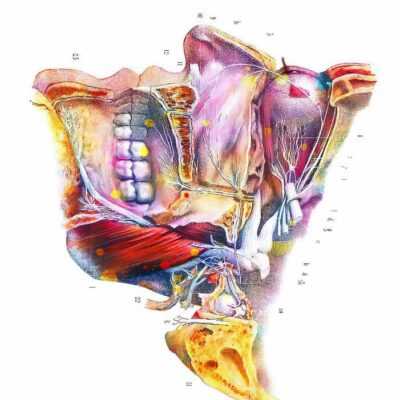

Tableaux murale pour la décoration intérieure d’un cabinet médical dentiste